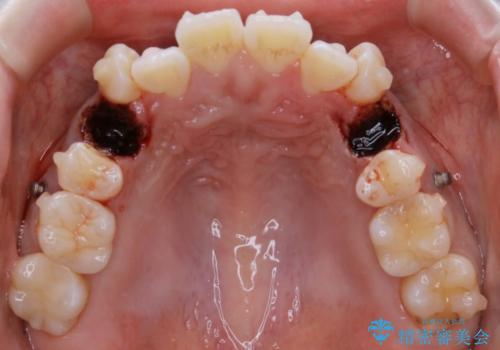

- 前歯のガタつき・噛み合わせの不調を主訴にご来院されました。

患者様のお仕事柄、目立たない装置で矯正したいとのご要望があり、今回はインビザラインを用いて抜歯矯正を行うこととなりました。

本来、抜歯によって得られる大きなスペースのコントロールはワイヤー装置の方が得意とされていますが、こちらの患者様のように犬歯が大きく手前に傾斜していて奥歯の噛み合わせにそれほど問題がないケースではマウスピース装置でも十分にコントロールできることが予測されます。

歯のガタつきの度合いが強い場合や、上下で大きく噛み合わせがズレている時などに、その改善のための大きなスペースを作る代表的手段が「抜歯」です。

一般的には第一小臼歯(犬歯の一つ隣の歯)を抜くことが多く、前歯のガタつきを改善したり口元を引っ込める場合に利用されます。